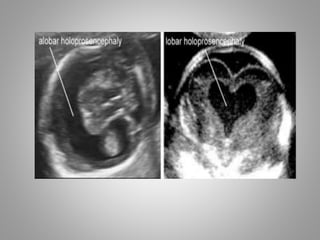

Types Of Holoprosencephaly

3 Types

Alobar

Cerebrum appears as single entity.

Semilobar

Partial attempt to form 2 hemispheres.

Lobar

2 hemispheres are formed but midline structure

is abnormal.

Usg Features

• Alobar and Semi-lobar types show absence of

falx and absent or non fused thalami.

• Alobar has 3 sub variants

1. Pan cake -Thin plate of cerebrum with large

dorsal Cyst

2. Cup - somewhat more tissue of cerebrum

with dorsal cyst

3. Ball – single mono-ventricle surrounded by

brain tissue of varied thickness.

• Lobar Holoprosencephaly – this subtype is

difficult to diagnose, b/c

both hemispheres are present

falx is present

• But midline structures like CC , Speti Pellucidi &

thalamus not found.

• Absence of Septi pellucidi will cause frontal Horn

of Lat. Ventricle to appear close to eachother

giving a square shaped and fused apperance.

• Diffrential Diagnosis- Septo-optic dysplasia